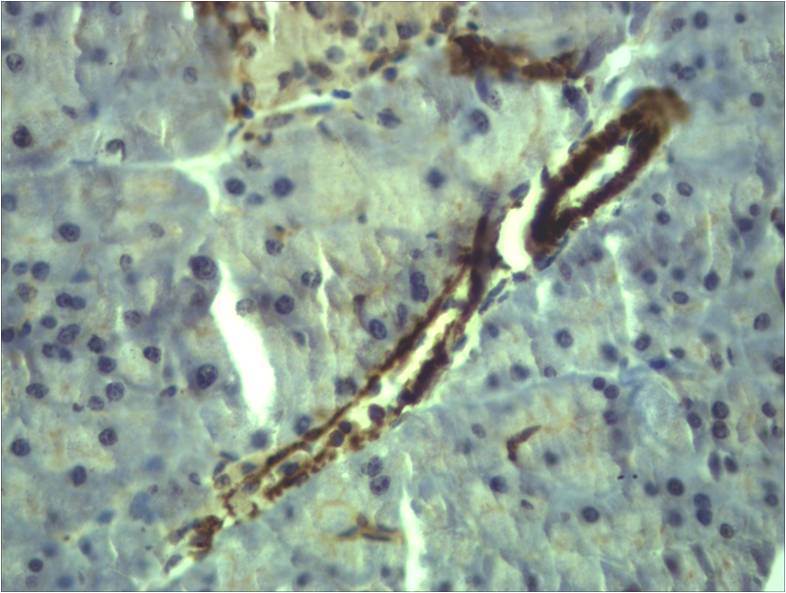

Product name: α-Smooth Muscle Actin Rabbit pAb

Reactivity: Human, Rat, Mouse

Dilutions: WB 1:2,000-5,000? IHC 1:500-1,000

Background: Actin is a globular multi-functional protein that forms microfilaments. ACTA2 codes for an α-actin located in the smooth muscle, and also in vascular smooth muscle.